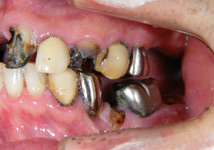

| 長年放置したために歯周病が進行し噛みにくくなった患者様が、インプラントを入れ全顎的な治療を行い審美改善しました。今はよく噛めるようになったと喜んでいらっしゃいます。 |

|